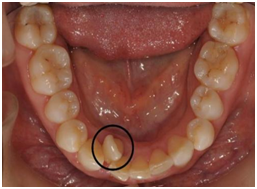

成员二:双排牙

双排牙出现大多是因为牙齿排列拥挤,也就是牙齿数量、大小和骨骼大小不协调造成的(牙齿多、颌骨小)。他们会影响面部美观和前牙功能,还会造成口腔清洁不到位,继而形成龋齿,下前牙的“双层牙”表现会随着下颌智齿的萌出变得更加明显。

“双排牙”这种情况是可以通过替牙期适当的咀嚼训练,去除吮指、嘬腮等不良习惯减轻、甚至避免的。